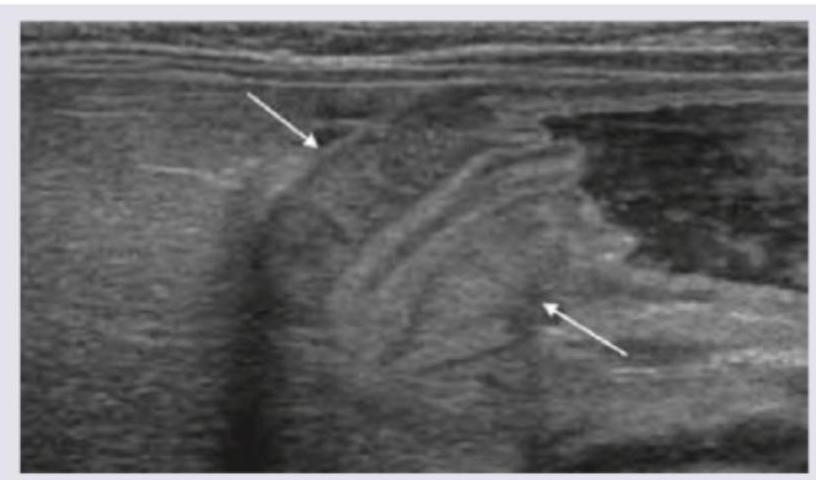

Explanation: ***b.Caused by hypertrophy of longitudinal muscles***- The defining pathology of congenital hypertrophic pyloric stenosis involves hypertrophy and hyperplasia of the **circular muscle layer** of the pylorus, not the longitudinal muscle layer.- This thickening of the circular muscle narrows the pyloric canal lumen, leading to gastric outlet obstruction.*a.Presents with non-bilious vomiting*- This is a true statement; vomiting is typically **non-bilious** because the obstruction is proximal to the **ampulla of Vater** (where bile enters the duodenum).- The vomiting is often projectile, feeding soon after a meal, and progresses from occasional to nearly every feed.*c.USG is very sensitive in diagnosing this condition*- This is a true statement; ultrasonography is the diagnostic modality of choice due to its high sensitivity and specificity, avoiding radiation exposure.- Diagnosis is confirmed when the **pyloric muscle wall thickness** is >4 mm or the **pyloric channel length** is >16 mm.*d.Hypokalemic metabolic alkalosis seen*- This is a true statement; persistent, massive vomiting leads to the loss of gastric **hydrochloric acid (HCl)**.- The resulting primary loss of H+ ions leads to **metabolic alkalosis**, which is compensated by renal excretion of K+ and retention of HCO3- (leading to secondary **hypokalemia**).

Explanation: ***Palpation of lump*** - In pyloric stenosis, the hypertrophied pylorus can often be palpated as an **olive-shaped mass** in the right upper quadrant or epigastrium. - This palpable mass upon abdominal examination is considered the most **crucial diagnostic finding** for pyloric stenosis. *Visible peristalsis* - While **visible peristaltic waves** (particularly from left to right across the epigastrium) can be a sign of pyloric stenosis, they are not specific or the most essential diagnostic feature. - Visible peristalsis indicates an attempt by the stomach to force contents past an obstruction, but its presence can vary and may not be consistently observed. *Projectile vomiting* - **Projectile non-bilious vomiting** is a classic symptom of pyloric stenosis, suggesting a significant outflow obstruction. - However, symptoms alone are not as definitive for diagnosis as the physical finding of the "olive-shaped" mass, as other conditions can also cause severe vomiting. *Loss of weight and dehydration* - **Weight loss** and **dehydration** are common consequences of persistent vomiting due to pyloric stenosis, indicating disease progression. - These are systemic effects reflecting the severity of the condition rather than a direct diagnostic feature of the underlying anatomical abnormality.